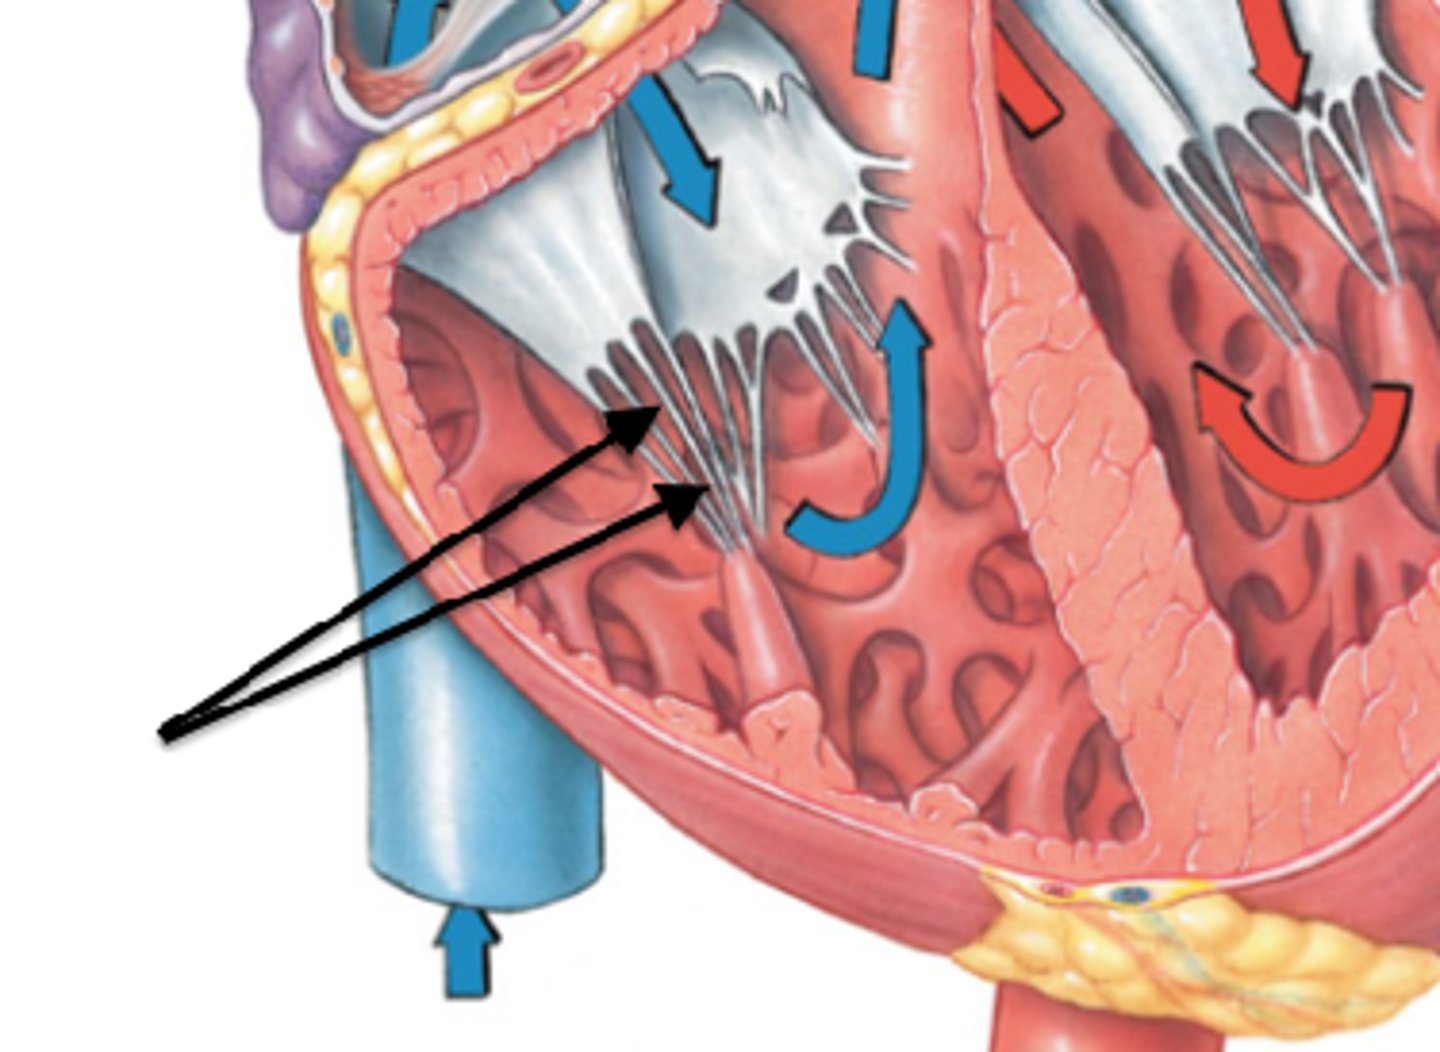

tricuspid valve

3 cusps. closes as pressure rises in the ventricle to prevent backflow of blood

papillary muscles (3)

they tug at your heart strings

tendinous cords

heart strings

trabeculae carneae

ridges of cardiac muscle

pulmonary valve

valve between the right ventricle and pulmonary artery

semilunar cusps

half moon shaped flaps of the endocardium

mitral valve

valve between the left atrium and the left ventricle; bicuspid valve

aortic valve

all three cusps make up the...